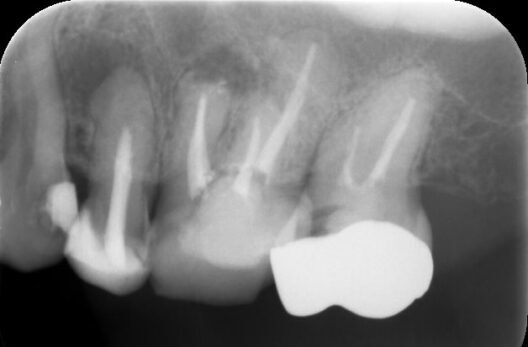

治療前レントゲン

術前レントゲン

レントゲン上で、左上5番目に歯の根の先に黒い透過像(赤い丸)が認められ、叩いた時の痛みなどの検査から、患歯が特定できましたので、根の治療(根管治療)を行うことになりました。